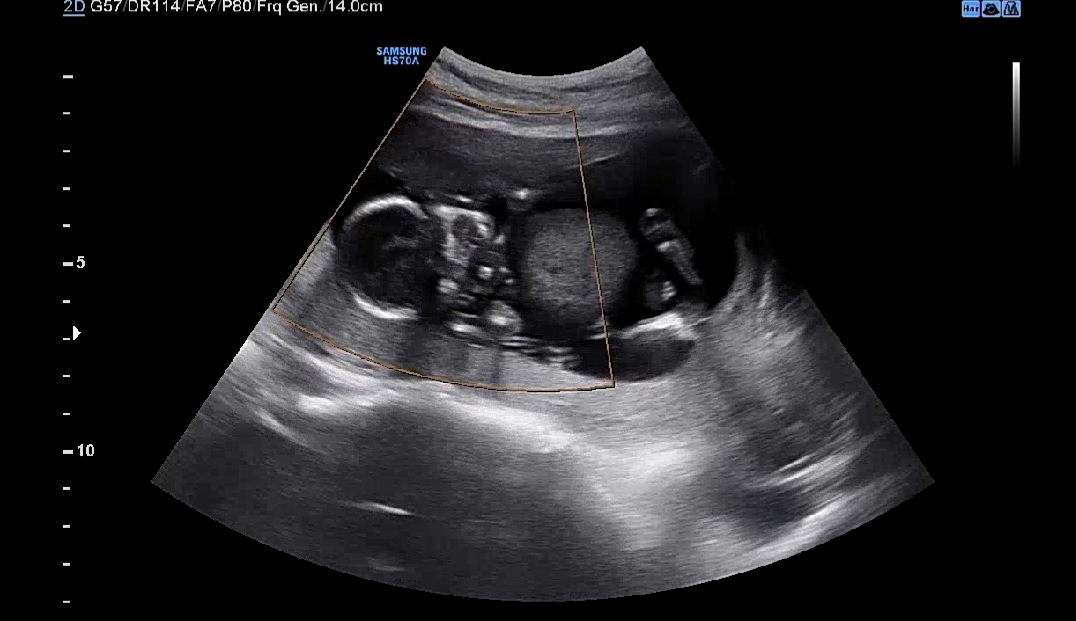

제 자궁이 너무 좁은걸까요?

어떤분 촘파 사진 보니 아이가 다리를 일직선으로 쭉 뻗고있던데 같은주차수인 저희아이는 몸을 쭈구리고 있는 느낌이여서요 ㅠㅠ 제 자궁이 작은걸까요? 아이가 좁아서 몸을 웅크리고있는 느낌일까요?

초음파가 다 못잡기도 하나보더라고요 저도 애기가 너무 꽉끼어 있는게 아니냐고 여쭤보니 뒤쪽공간(?)도 보여주시면서 다 안보여서 그런거리고 말씀 해주시더라고요!

의사샘께서 아기집 작다고 하신거 아니면 괜찮지 않을까용? 저희 애기두 사이즈가 커지니까 다리 접고 있다가 쭉 펴면서 배에 꾹꾹이도 하고 그러더라구요ㅋㅋ

저도 며칠전 병원에서 촘파볼때, 애기 집이 좁아보여서 선생님께 말씀드렸더니, 성장을 방해할 정도는 아니지만 작은 편이라고 물을 많이 마시라고 하셨어요. 꼭 물이 아니라고 이온음료나 카페인 없는 차도 좋다고 하셨구요. ㅎㅎ 아무래도 양수니까 물이 많이 필요한 건지.. 그날 부터 물 많이 마시고 있어요 ㅎㅎ 방평수 넓혀주려구요.